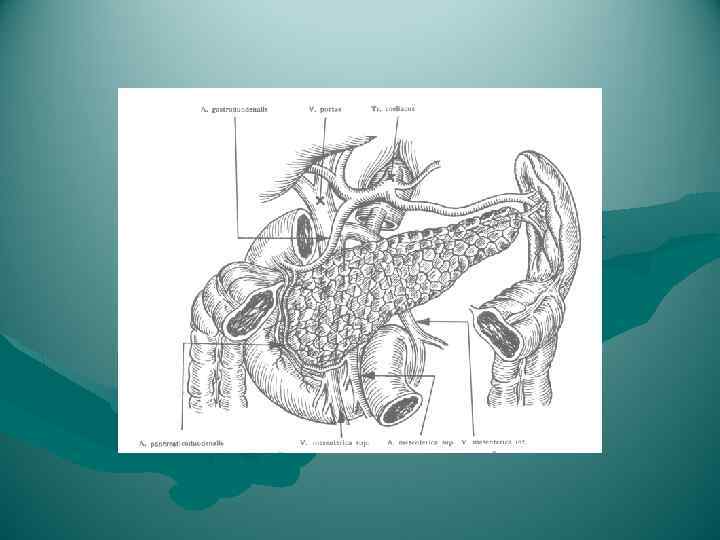

Кровоснабжение головки поджелудочной железы осуществляется из передней и задней артериальных дуг, образованных двумя верхними (из a. gastroduodenalis) и двумя нижними (от начального отдела a. mesenterica superior) панкреатодуоденальными артериями. От каждой из названных дуг в паренхиму головки отходит от 3 до 7 артерий. Тело и хвост поджелудочной железы снабжаются кровью из rr. pancreatici от селезеночной артерии. Отток венозной крови происходит непосредственно в воротную вену и ее главные притоки — vv. lienalis et mesenterica superior.

Кровоснабжение головки поджелудочной железы осуществляется из передней и задней артериальных дуг, образованных двумя верхними (из a. gastroduodenalis) и двумя нижними (от начального отдела a. mesenterica superior) панкреатодуоденальными артериями. От каждой из названных дуг в паренхиму головки отходит от 3 до 7 артерий. Тело и хвост поджелудочной железы снабжаются кровью из rr. pancreatici от селезеночной артерии. Отток венозной крови происходит непосредственно в воротную вену и ее главные притоки — vv. lienalis et mesenterica superior.